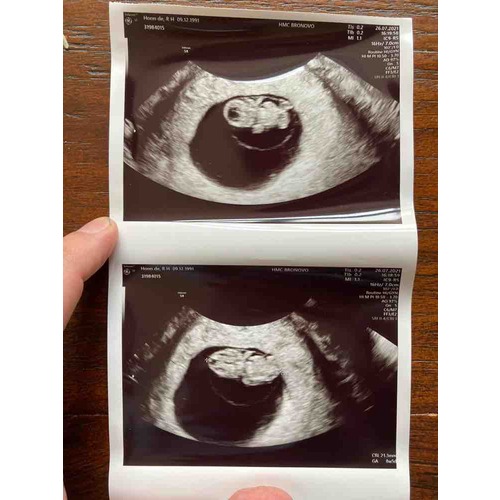

Haii hier was ik 8+3 Je ziet een klein beetje de stompjes waar de armpjes komen en links zijn de billetjes 馃槂 Het is zo bijzonder en mooi om al zo鈥檔 klein hartje te zien kloppen 馃グ